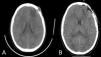

Un niño de 11 años presentó aumento de volumen en la región frontal izquierda, sin déficit neurológico ni síntomas sistémicos. La tomografía y la resonancia magnética revelaron una lesión osteolítica agresiva con edema perilesional y extensión intracraneal.

An 11-year-old boy presented with increased volume in the left frontal region, without neurological deficit or systemic symptoms. CT and MRI revealed an aggressive osteolytic lesion with perilesional edema and intracranial extension.